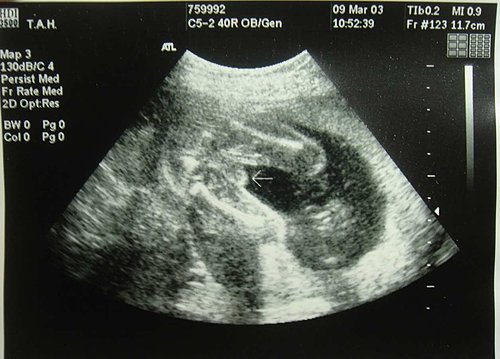

在這一天

我們一家人去醫院跟肚子裡的Omyga見面